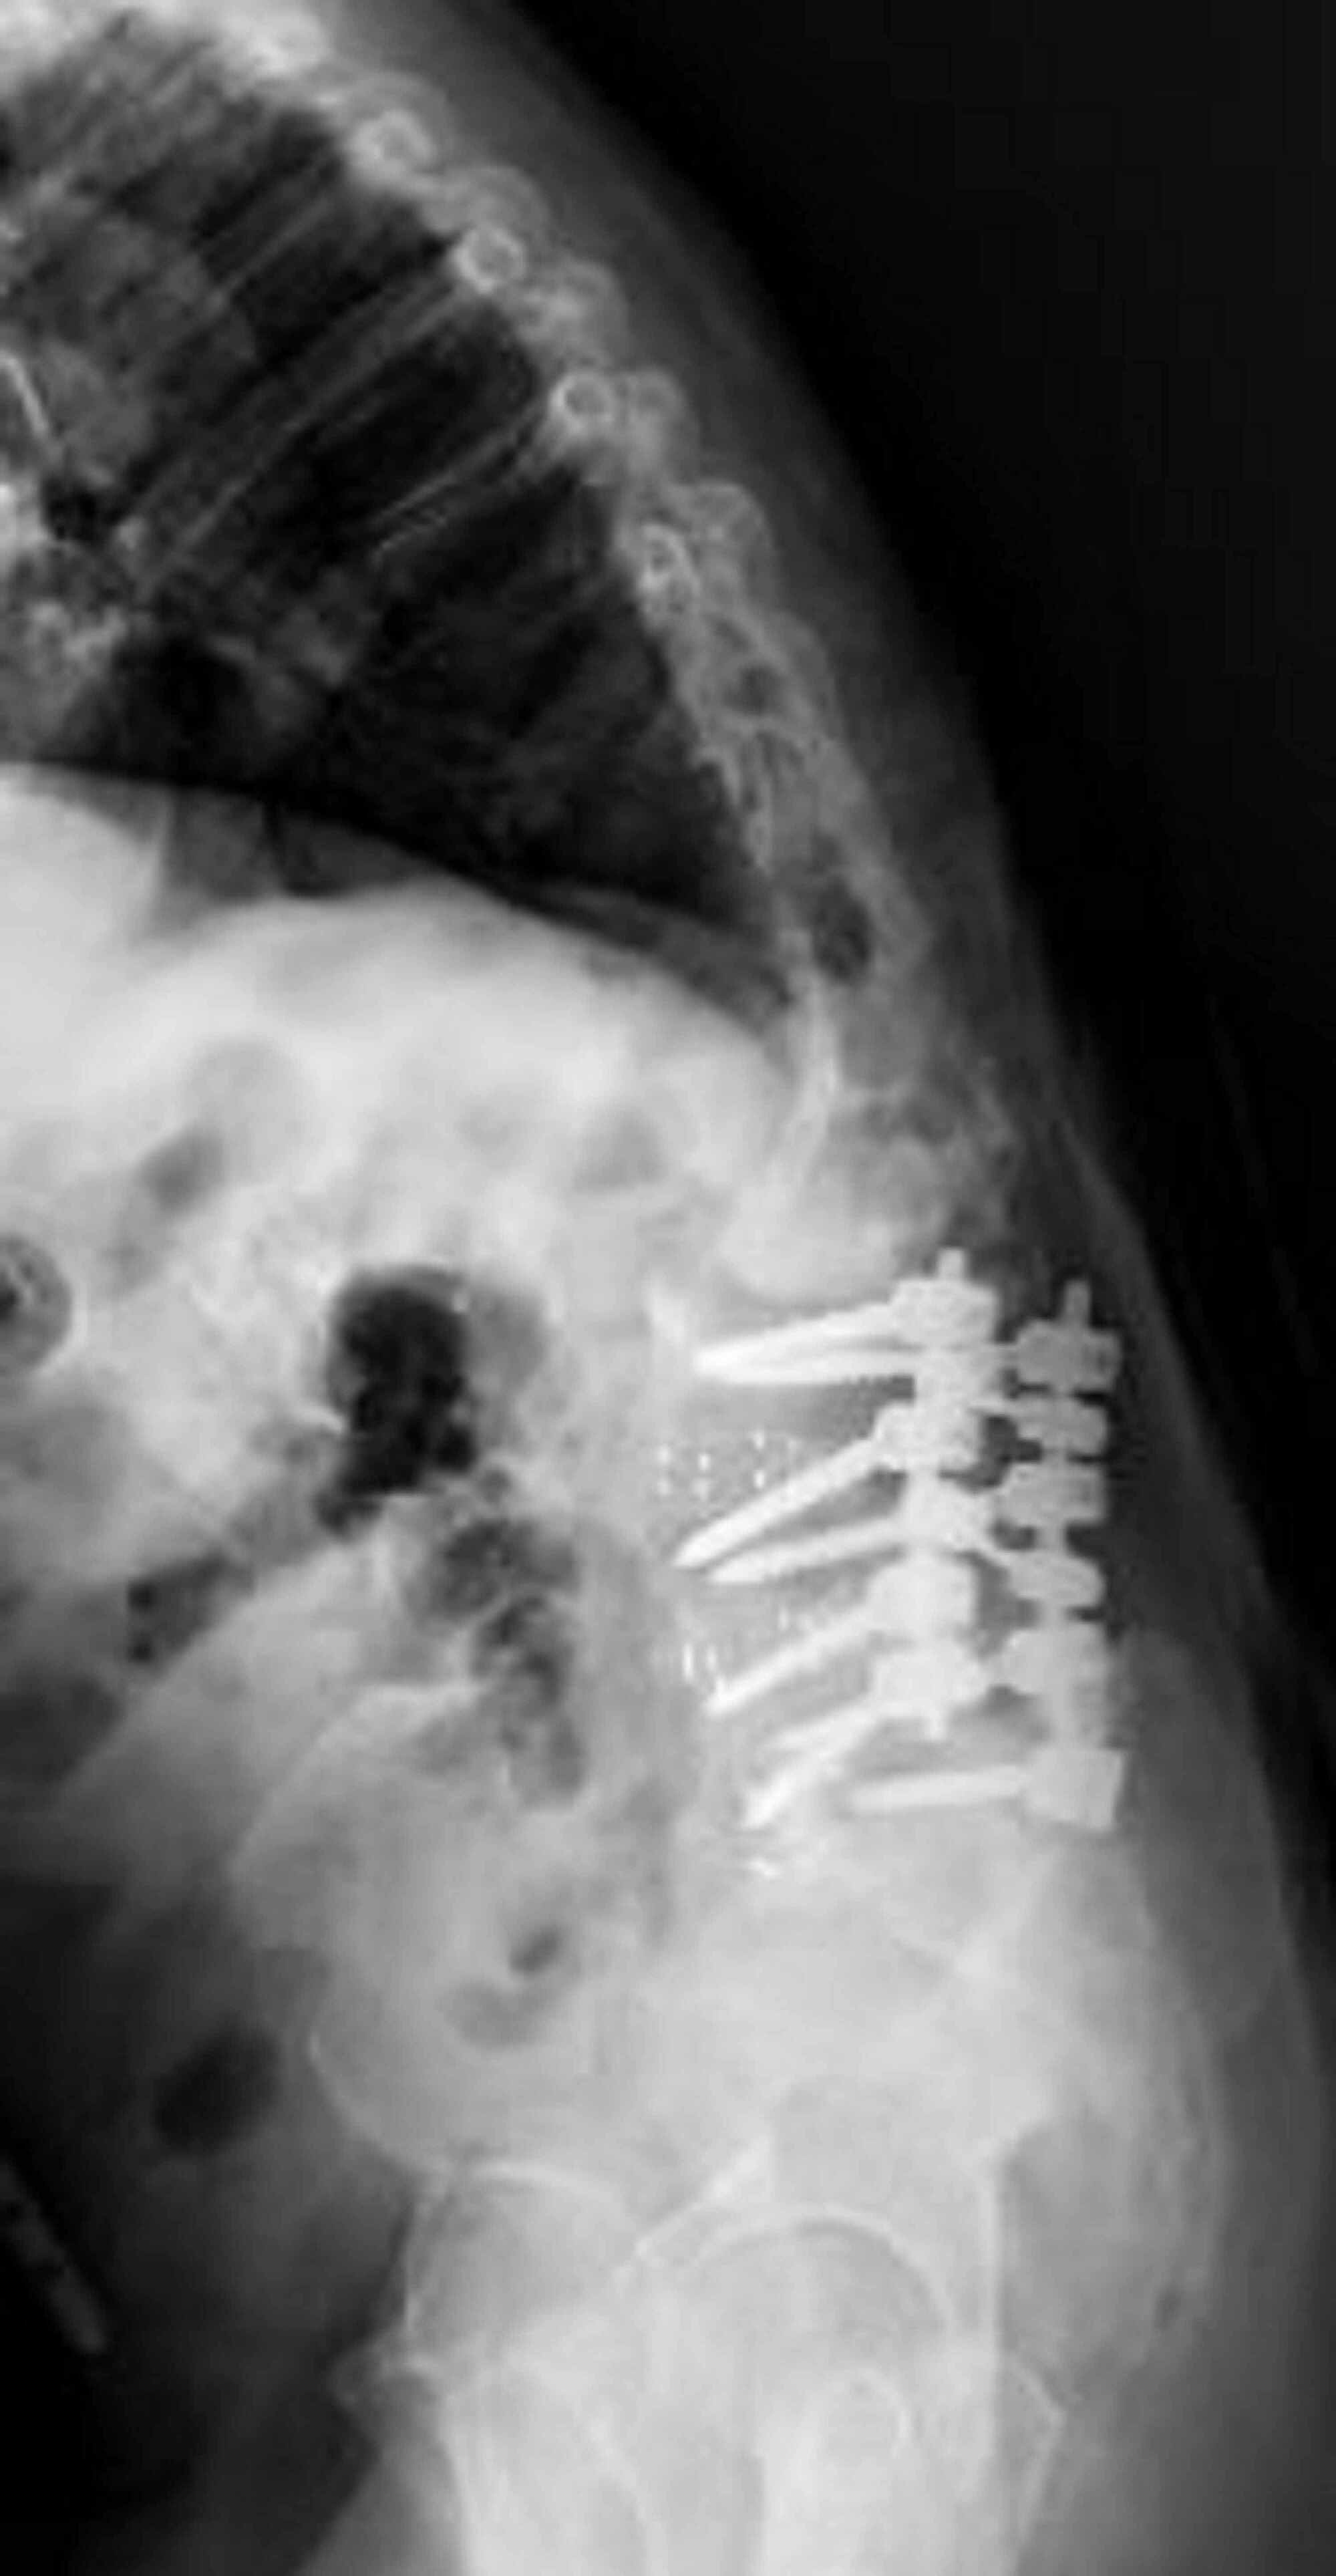

Radiographs demonstrating the application of the kickstand rod Kick Stand Rod This technique was found to provide. Only few studies about the coronal alignment correction with the kickstand rod were reported in the literature, until now. The aim of the present. This study tested the hypothesis that the kr technique provides. New surgical procedure for correction of coronal imbalance (ci) in spinal deformity patients. The objective of this study was to. Kick Stand Rod.

Case 4. This is a case of Type 2 CM. The kickstand rod technique Kick Stand Rod Only few studies about the coronal alignment correction with the kickstand rod were reported in the literature, until now. The kickstand rod technique is safe and effective for the correction of ci in spinal deformity patients. The objective of this study was to describe and evaluate a new surgical procedure for the correction of coronal imbalance (ci) in. The aim. Kick Stand Rod.

Radiographs demonstrating the application of the kickstand rod Kick Stand Rod This study tested the hypothesis that the kr technique provides. New surgical procedure for correction of coronal imbalance (ci) in spinal deformity patients. The kickstand rod technique is safe and effective for the correction of ci in spinal deformity patients. The kickstand rod technique has been described as a novel technique for cm correction using an accessory rod on the.. Kick Stand Rod.

Radiographs demonstrating the application of the kickstand rod Kick Stand Rod The kickstand rod (kr) technique is powerful for correcting truncal shift. The kickstand rod technique is safe and effective for the correction of ci in spinal deformity patients. This study tested the hypothesis that the kr technique provides. This technique was found to provide. New surgical procedure for correction of coronal imbalance (ci) in spinal deformity patients. The kickstand rod. Kick Stand Rod.